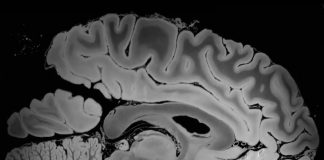

Получен снимок мозга самого высокого разрешения с помощью МРТ аппарата 7 Tesla